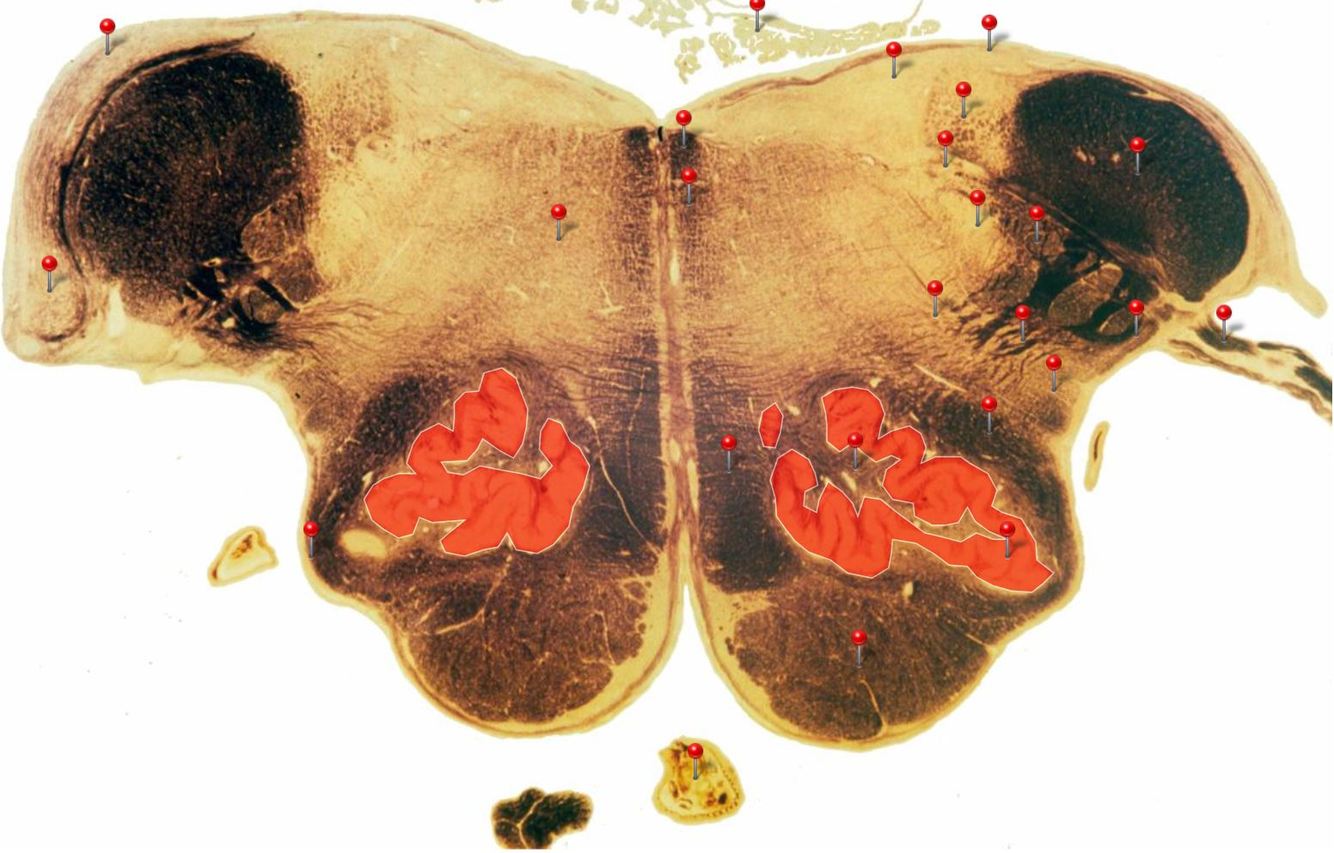

Caudal Midbrain

Transmits auditory info from the inferior colliculus to the medial geniculate nucleus of the thalamus

Corticospinal Tract

Controls precision and speed of skilled movements involving the distal muscles of the contralateral limbs, particularly those of the hands and fingers

Rubrospinal Tract

Assists in the control of movements of the hands and fingers

Oculomotor Nucleus

Neurons give rise to GSE fibres of the oculomotor nerve (CN III) which supply extraocular muscles (4 out of the 6, as well as some fibres of the levator palpebrae superioris m.)

Spinothalamic Tract

Transmits pain and temperature sensations from the spinal cord to the thalamus

Superior Colliculus

Important relay centre for visual reflexes

Periaqueductal Gray (PAG)

Important centre in modulating pain transmission in the spinal cord, particularly in conditions of extreme stress (indirectly through connections with reticular formation)

Medial Longitudinal Fasciculus

Pathway through which eye movements are coordinated with changes in head position